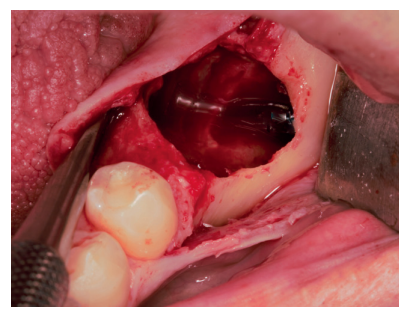

En una primera fase, se llevó a cabo la extracción del 3.7 y se empleó el mismo diente para realizar una preservación del defecto. Se realizó una anestesia troncular del nervio dentario inferior, nervio lingual y nervio bucal del lado izquierdo con articaína al 4% y adrenalina 1: 100,000 (Ultracaine®, Normon SL, Madrid, Spain). Se procedió a realizar una incisión supracrestal sin descargas y un despegamiento mucoperióstico a espesor total, asegurando la protección del colgajo lingual (Figura 3). Se realizó odontosección coronal para facilitar su extracción y, una vez removidas las raíces, se regularizaron los bordes y se dejó preparado para recibir el injerto (Figura 4).